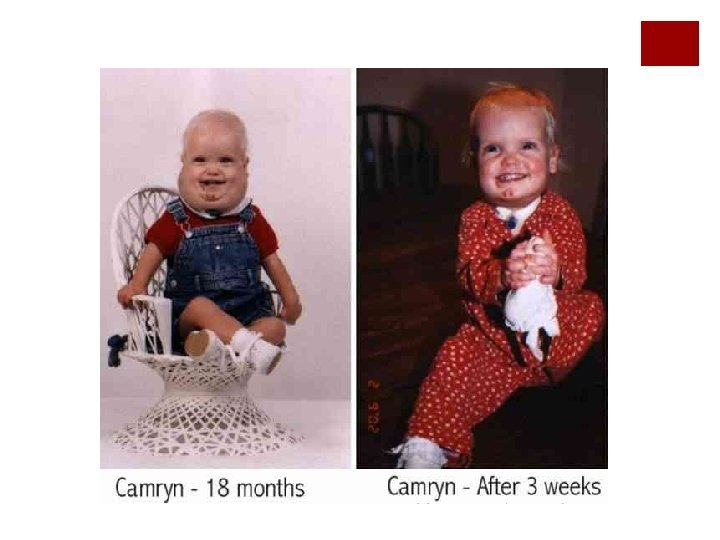

HEMANGIOMAS ¡Los mas frecuentes de la infancia ¡M >H 3: 1 ¡ 60% en cabeza y cuello ¡Niños con múltiples lesiones cutáneas se asocian a hemangiomas viscerales (hígado, pulmón y TGI) RN 6 -10 m Prolif eración Involución 5 años 7 años 50% 70%

HEMANGIOMAS SUBGLÓTICOS Y TRAQUEALES ¡Benignos, derivados de tejido mesodérmico ¡ 1. 5% de las lesiones laríngeas ¡M > H 2: 1 ¡RN: Asxs / 6 meses: estridor y obstrucción vía aérea ¡ 50% cursan con hemangiomas cutáneos ¡ 30 a 70% de mortalidad sin Tto